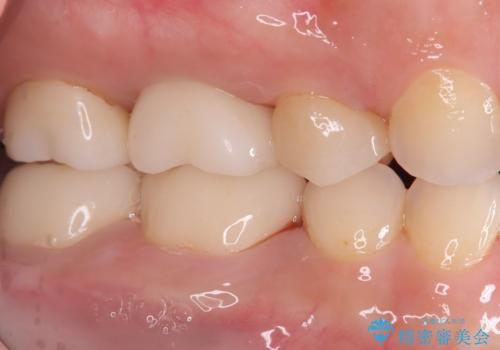

- 右下6番と7番の奥歯に、歯の根元部分の虫歯(根面カリエス)を認め来院されました。通常の虫歯よりも進行しやすい根面カリエスは、再発リスクを抑えた治療が重要です。患者様のご希望と口腔内の状態を考慮し、虫歯を徹底的に除去し、精密で耐久性の高いセラミッククラウンで修復する治療計画を立案しました。これにより、長期的な再発防止と咬み合わせの機能回復を目指します。

治療ではまず、感染した歯質をマイクロスコープで確認しながら慎重に除去。その後、セラミッククラウンを装着するための歯の形成を行いました。型取りから患者様の歯の形や色に合わせたオーダーメイドのセラミッククラウンを作製。セラミックは、プラークが付着しにくく、再治療のリスクを低減する特性があります。最終的に、精度の高いクラウンを装着し、咬み合わせを細かく調整しました。これにより、根面カリエスが再発しにくい環境を整え、快適に食事ができる奥歯を取り戻していただけました。